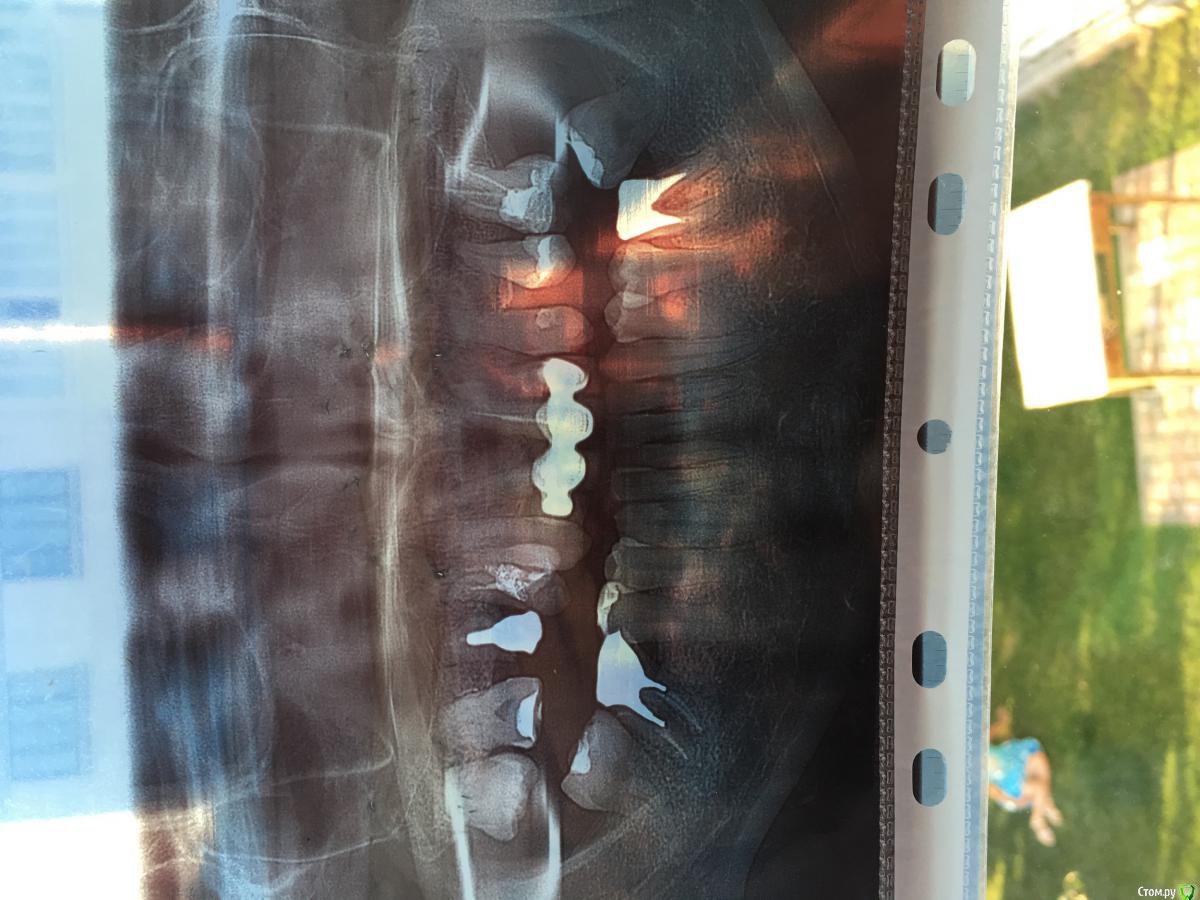

Ярослава0811 Опубликовано 10 июля, 2018 Поделиться Опубликовано 10 июля, 2018 Добрый вечер! Вопросы: 1. Нужно ли перелечивать корни верхних фронтальных четырёх зубов? Ставлю новые коронки, на консультации один врач сказал, что есть большая гранульома и нужно лечить. Другой ничего фатального там не увидел, хотел добраться и перепломбировать один з зубов, но не смог так как канал плотно запечатан. Сказал, что не доберётся и так сойдёт ...2. Можно ли на левую верхнюю четвьорку ставить имплант? Там очень мало места, врачи говорит что лучше мост...(3. Нужно ли удалять левый нижний корень с вкладкой? Один врач говорит, что корень сгнил и нужно удалять, другой, что он ещё простоит лет 10 минимум... Спасибо заранее за консультацию!!!! Ссылка на комментарий

St. Опубликовано 10 июля, 2018 Поделиться Опубликовано 10 июля, 2018 Добрый вечер. Лучше всего сделать дополнительно КТ, по ней будет видно точно есть ли воспаление около корней на передних верхних зубах( и соответственно нужно ли там перелечивать каналы). Можно ли на левую верхнюю четвьорку ставить имплант? Места действительно мало, за счет того что зуб долго отсутствовал соседи сместились. Можно с помощью брекетов отодвинуть дальние зубы в исходное положение и потом поставить имплант Нужно ли удалять левый нижний корень с вкладкой? Вы не путаете расположение?По счнимку вопросы вызывает верхний 5 справа с вкладкой. Он разрушен очень сильно. Смысла вкладывать финансы в его перелечивание и протезирование нет, я бы рекомендовала удалить Ссылка на комментарий